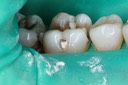

Kyle Chock #19 pre-op